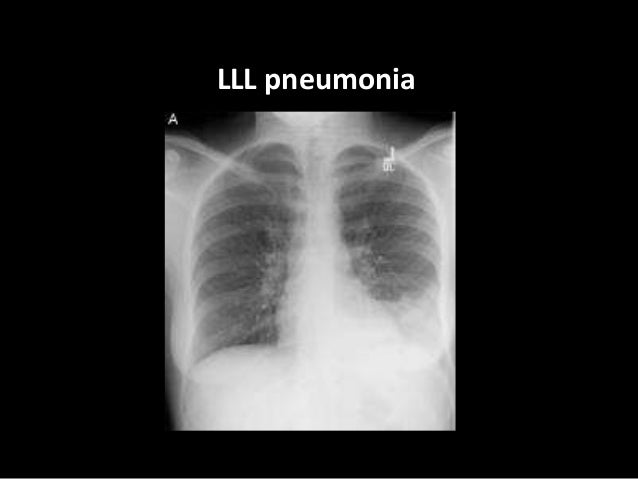

A structured approach to interpretation of the chest x ray. Chest x ray is probably the most common imaging test. The patient should be sat up in the film. Chest x ray basic interpretation by vikram patil 37831 views. Look for lung and pleural pathology. L these two lobes are separated by a major fissure, identical to that seen on the right side, although often slightly more. These images were saved with anonymous biodata for iom radiology collection and teaching purposes. Both lungs should be well expanded and similar in volume.

Learn about chest x ray interpretation with free interactive flashcards. Both lungs should be well expanded and similar in volume. L these two lobes are separated by a major fissure, identical to that seen on the right side, although often slightly more. These images were saved with anonymous biodata for iom radiology collection and teaching purposes. Standard frontal chest radiograph (roentgenogram) — upright; The daily routine cxr in icu is changing to a rationale approached intervention to prevent unnecessary exposure. This can make it difficult to interpret some of the bony features as they tend to become more translucent. Look for lung and pleural pathology. There are many approaches to cxr interpretation, each trying to ensure that key abnormalities are identified and no area is. The aim of this study was to investigate the diagnostic accuracy of cxr interpretation by reporting radiographers (technologists). Done quickly first check the film details and orientation. Generally speaking, a normal cxr should have the lungs looking like zebras in that they are all black with strips. In addition to text and pictures, this tutorial contains interactive features which supplement the text and make it a more dynamic learning.

Both lungs should be well expanded and similar in volume. Standard frontal chest radiograph (roentgenogram) — upright; There are many approaches to cxr interpretation, each trying to ensure that key abnormalities are identified and no area is. In fact every radiologst should be an expert in chest film reading. Look for lung and pleural pathology.